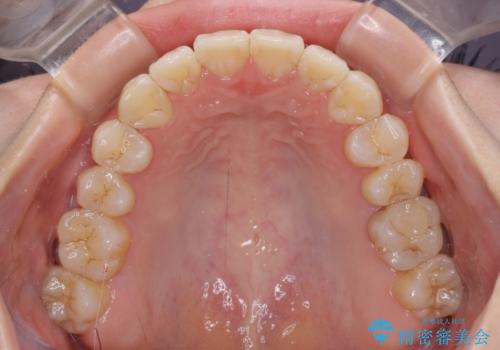

前歯にデコボコがあり、口元がやや突出した印象があったため、IPR(歯と歯の間を削る)と親知らずを抜歯した上での歯列全体の後方移動をメインに、インビザラインを用いて矯正治療を行うこととしました。

年に一度、夏休みの時期にしか帰国できないため、帰国のタイミングに合わせてマウスピース交換スケジュール治療計画としたため、3年半という期間を要しました。

留学先でもしっかりとマウスピースの装着を実践してくださったので、ご本人の満足のいく仕上がりとなりました。